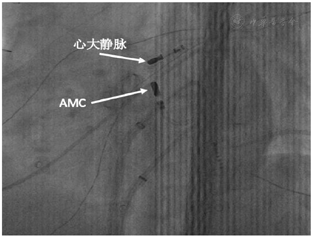

患者室性早搏来源于位置较高的Summit区域,在左冠窦区未标测到较早的V波,遂考虑至邻近的结构中继续寻找靶点,如心内膜的主动脉窦-二尖瓣连接处(AMC)或心外膜的心大静脉/前室间静脉区或右室流出道后部,但患者有主动脉瓣置换史,无法跨主动脉瓣至AMC进行标测,遂穿刺股静脉,置入Swartz L1长鞘将大头电极送至心大静脉远端,行激动顺序标测,在心大静脉区域标测到较QRS波提前26 ms的V波(图2),设置功率20 W,流速40 ml/min,在此处消融有效,室性早搏消失,消融过程温度达35~41℃。但点滴异丙肾上腺素后仍能诱发室性早搏。